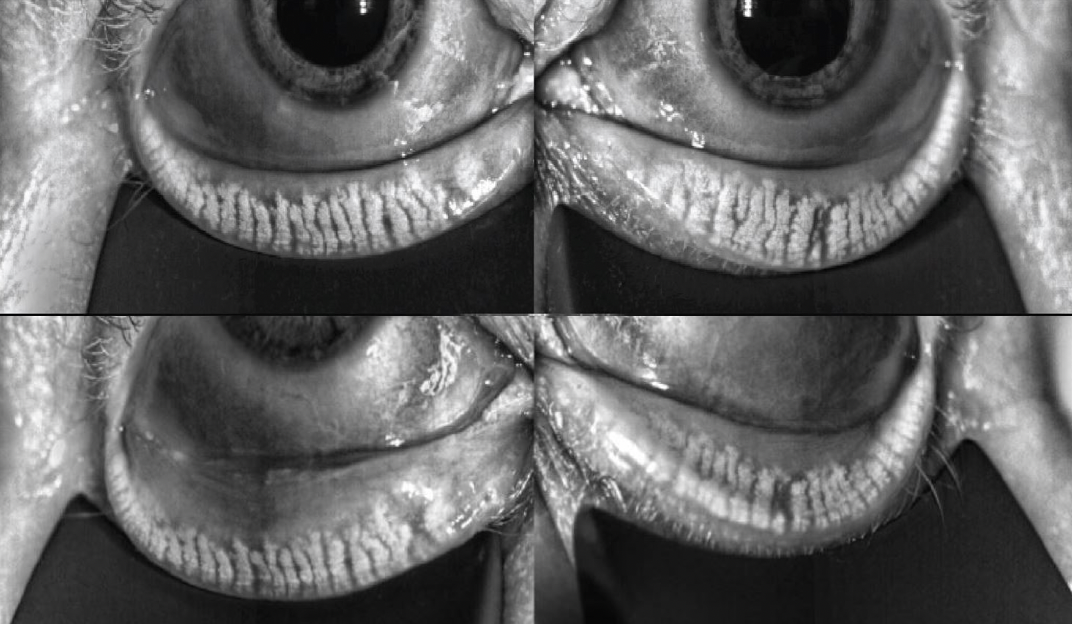

It's not always easy to convince early-stage, minimally symptomatic or symptomatic patients that their MGD should be treated. Cynthia Matossian, MD, FACS, explains why ophthalmologists shouldn't take this personally and how not to accept their denial as a final answer.